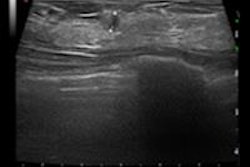

Mammography loses sensitivity in women with dense breast tissue, and other modalities such as breast MR and ultrasound are used to find cancers that mammography misses in this population, noted presenter Dr. Per Skaane, PhD, from Oslo University Hospital in Norway. But MR and ultrasound also have higher false-positive rates than tomosynthesis -- which can result in unnecessary follow-up tests and biopsies.

The combination of FFDM and tomosynthesis had a cancer detection rate of 8.1 per 1,000 women, a 30% relative increase compared with FFDM alone, which had a rate of 6.1 per 1,000 women, the researchers found. In addition, the combination exam identified more cancers in denser tissue (BI-RADS 3 and 4) versus digital mammography alone: 80% versus 59%, respectively.